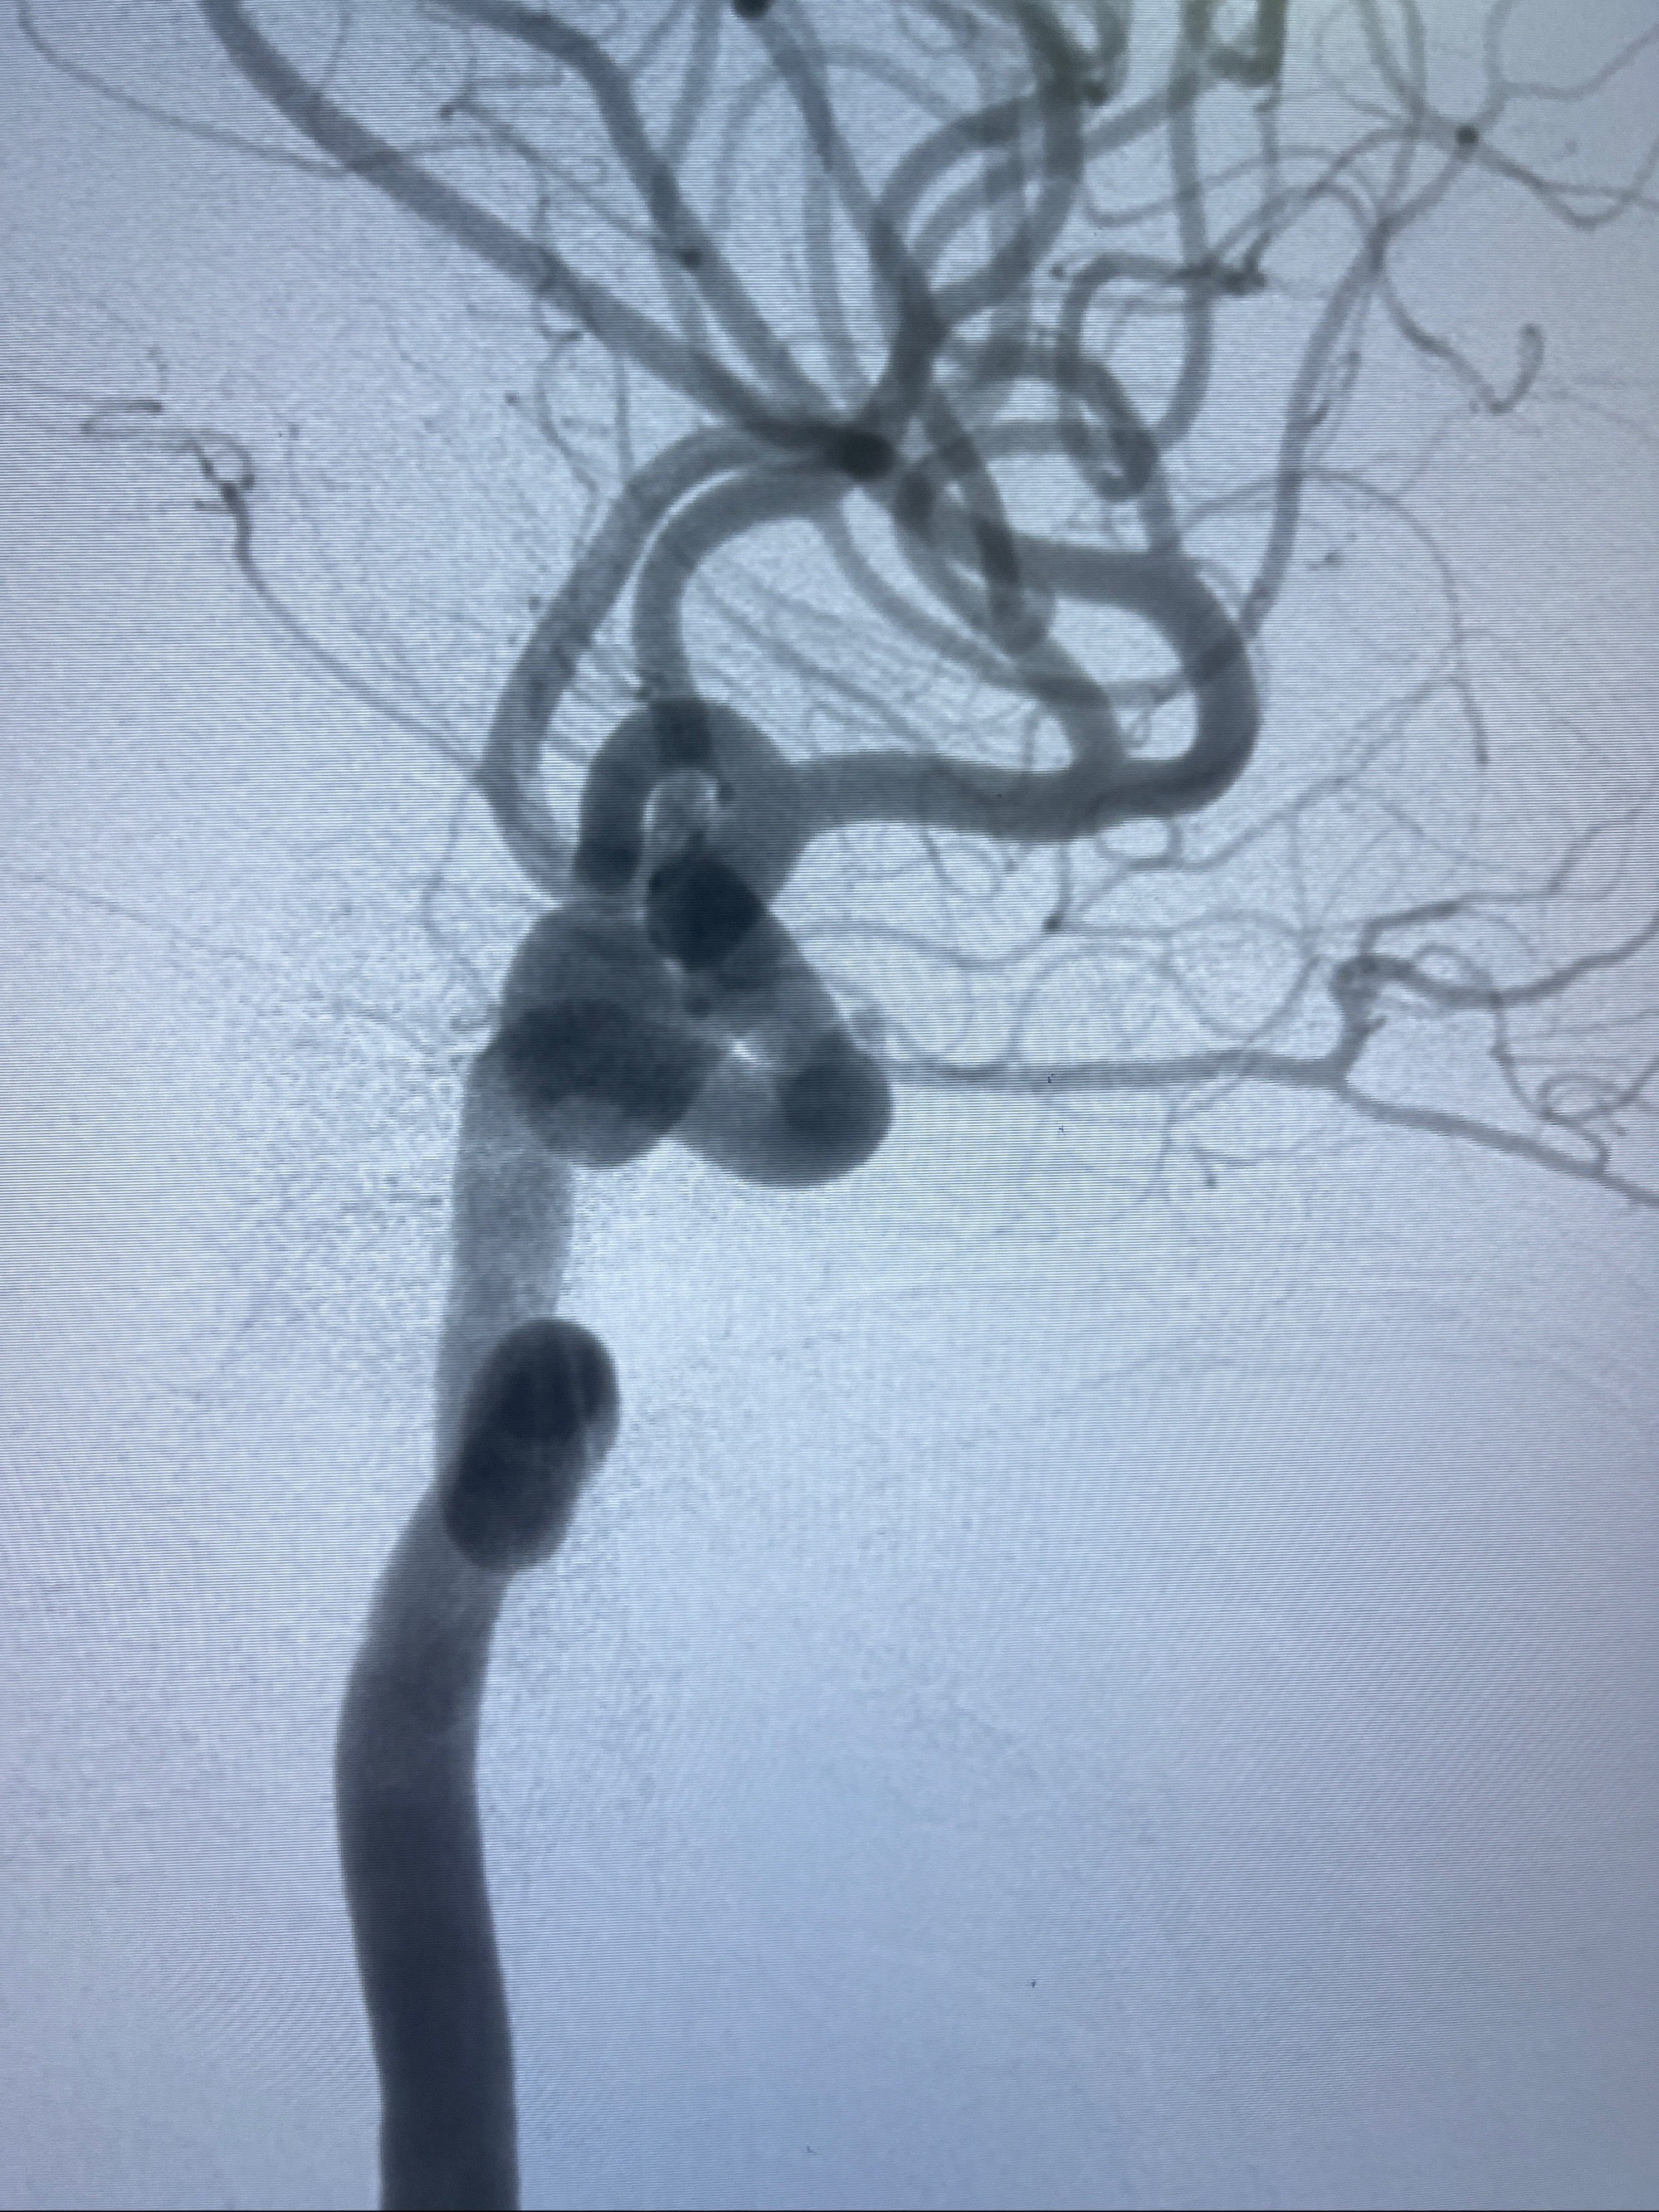

2023-08-30DSA:左侧颈内动脉眼动脉动脉瘤,约3*9.2*7.3mm大小

2023-09-06全麻下行左侧颈眼动脉瘤

密网支架辅助栓塞